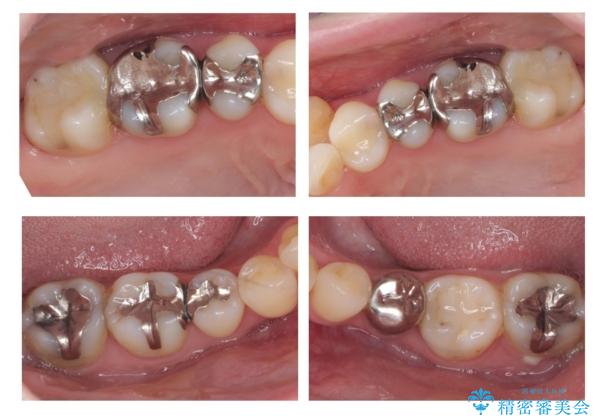

全体的な虫歯治療 銀歯をセラミックに

虫歯にならないようにするためにはしっかり精度の高い治療を行うことが大事です。

それと同時に歯ブラシをしっかりおこなうことや、食生活にも気を付けることが重要です。

毎食後の歯ブラシ、フロス、歯間ブラシをしっかり行うようにすると効果的です。

- 天然歯を削ります

- 硬い素材は天然歯を傷つけてしまう場合があります

- かみ合わせや歯ぎしりが強すぎる方はセラミックが割れてしまう可能性があります